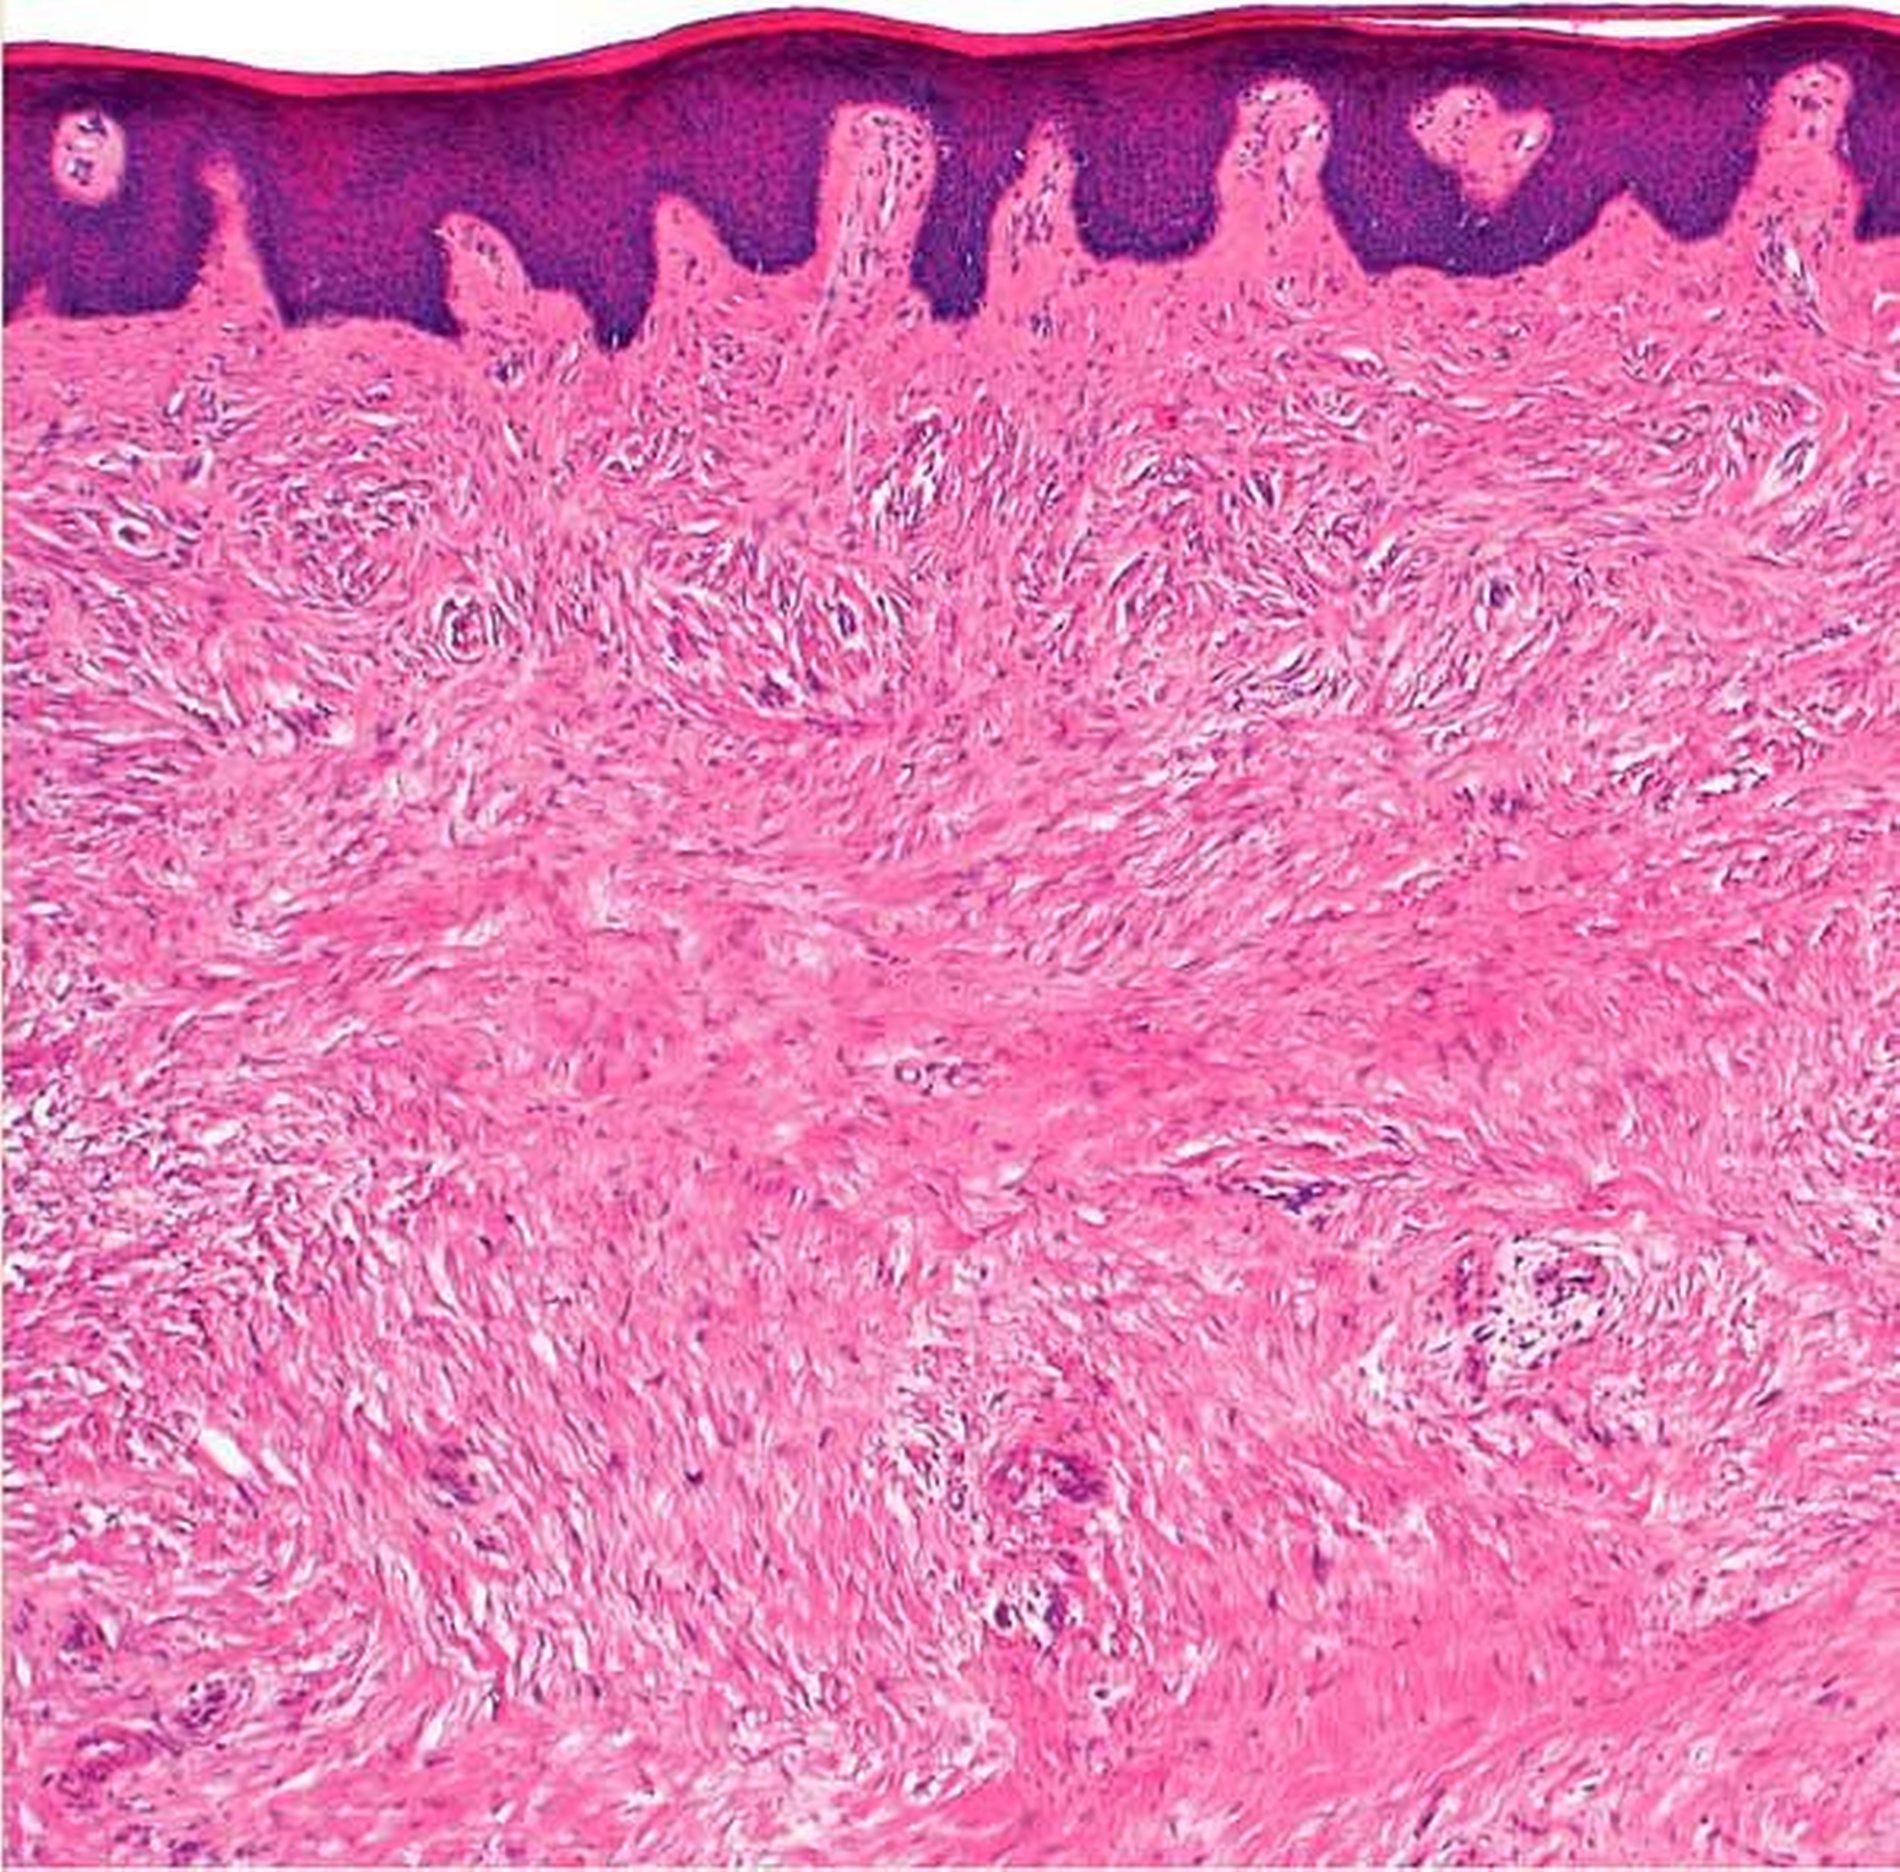

Die histopathologische Nachuntersuchung des Gewebeexzidats ergab den Befund eines echten polypösen Schleimhautfibroms ohne Anhalt für Malignität (Abbildungen 4a und 4b). Während der klinischen Nachsorge zeigte sich die per secundam ablaufende Wundheilung unter Zuhilfenahme einer Verbandsplatte und der täglichen Anwendung von 0,12-prozentiger Chlorhexidin-Mundspüllösung unter weiter bestehender immunsuppressiver Medikation und starkem Nikotinabusus zwar zeitverzögert, aber insgesamt unauffällig (Abbildung 5).

In den meisten Fällen handelt es sich um ein sehr langsames Wachstumsverhalten mit einer langen Bestehensdauer über mehrere Jahre [Mishra et al., 2017]. Im Zusammenhang mit dem oben genannten Fallbeispiel kann ein das Wachstum stimulierender Einfluss durch die synchrone immunsuppressive Dauertherapie und eine dabei akzeleriert ablaufende chronische Entzündungsreaktion nicht ausgeschlossen werden. Mikroskopisch zeigen Reizfibrome neben einem faserreichen Stroma mit einer entweder radiären oder zirkulären Kollagenfaseranordnung, zahlreichen spindelzelligen Fibroblasten und hyperkeratotischen Veränderungen regelmäßig Entzündungszeichen mit einer Invasion inflammatorischer Zelltypen [Mishra et al., 2017].

Echte Fibrome weisen im Vergleich eine eher ungeordnete Kollagenstruktur, eine scharfe Abgrenzung zu umliegenden Nachbarstrukturen sowie eine bindegewebige Kapsel auf [Patil et al., 2014]. Klinisch nicht immer eindeutig abzugrenzen, aber differenzialdiagnostisch zu berücksichtigen, sind zum einen gutartige Veränderungen wie das periphere Riesenzellgranulom, das periphere odontogene Fibrom, die fibröse Hyperplasie oder das peripher verknöchernde Fibrom sowie Läsionen wie das pleomorphe Adenom der kleinen Speicheldrüsen [Saka et al., 2014], die proliferative verruköse und die verrukiforme Leukoplakie.